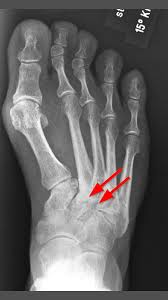

Fusswurzelarthrose Arthrose Des Lisfranc Gelenks Gelenk Klinik De

Fusswurzelarthrose Arthrose Des Lisfranc Gelenks Gelenk Klinik De from gelenk-klinik.de. Klick hier um mehr zu erfahren!